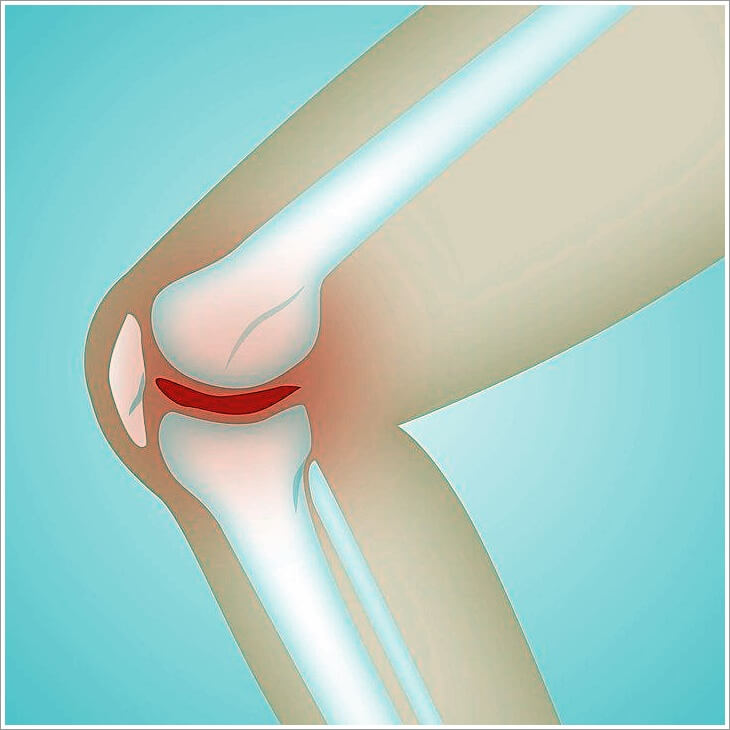

관절은 뼈와 뼈 사이가 부드럽게 운동할 수 있도록 연골, 관절낭, 활막, 인대, 힘줄, 근육 등으로 구성되어 있으며, 움직임에 따라 발생하는 충격을 흡수하는 역할을 한다. 관절염은 여러 가지 원인에 의해 관절에 염증이 생긴 것으로 이로 인해 나타나는 대표적인 증상은 관절의 통증이다.

관절 연골이 닳아 없어지면서 국소적인 퇴행성 변화가 나타나는 질환이다. 반복적인 작업이나 운동 등 연골을 오랜 세월동안 무리하게 사용하는 것, 비만으로 관절에 무리를 많이 주는 것, 관절 외상 등이 원인이 될 수 있다.

관절은 쓰면 쓸수록 닳는 신체 부위다. 특히 무릎은 우리 몸에서 하중 지탱으로 압력을 가장 많이 받는 부위라 관절염이 생기기 쉽다. 무릎 연골은 탄력이 있어 뼈와 뼈 사이에서 쿠션 역할을 해 마찰이 생기는 걸 방지해준다. 근육의 수축 및 이완 작용을 보조하는 역할을 하기도 한다.

정상적인 연골은 뼈 표면에 3~5mm정도로 푹신하고 미끌미끌한 형태를 유지하는데, 이 연골이 충격이나 과사용 등으로 벗겨지면, 관절이 스스로 보호하려는 염증 물질을 배출하면서 시리고 아픈 느낌이 생긴다 연골 중 무릎의 체중을 받쳐주는 반월상 연골이 손상되면 퇴행성관절염이 특히 잘 생긴다.

반월상 연골은 무릎에 전달되는 체중의 40~60%를 흡수해주고 관절 안정성을 유지하는데, 나이가 들수록 약해지며 쉽게 찢어진다.반월상 연골이 손상되면 무릎이 뻣뻣하거나 힘이 빠지는 느낌이 들지만 손상 부위가 작으면 초기에는 심각하지 않아 방치하기 쉽다.